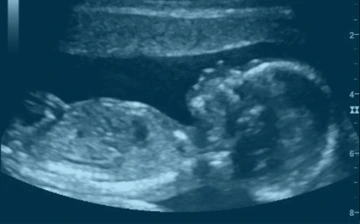

Confirmação da gestação e batimentos cardíacos

Ultrassons para avaliar crescimento e bem-estar fetal

Exame detalhado do bebê e da placenta com doppler

Avaliação da vitalidade e fluxo fetal com segurança

Ultrassom urgente com laudo e explicação no mesmo dia

Exame com registro audiovisual do bebê (sob consulta)

Confirma a gravidez

Avalia batimentos e localização

Ideal no 1º trimestre

Avalia crescimento fetal

Líquido amniótico e placenta

Desenvolvimento dos órgãos

Tônus, respiração e movimentos

Avaliação segura no 3º trimestre

Fluxo nas artérias uterinas e umbilicais

Rastreio de riscos de crescimento

Essencial em pré-natal de risco

Avaliação anatômica detalhada

Detecta malformações precoces

Inclui doppler fetal

Mede o colo do útero

Rastreia risco de parto prematuro

Rápido, seguro e essencial